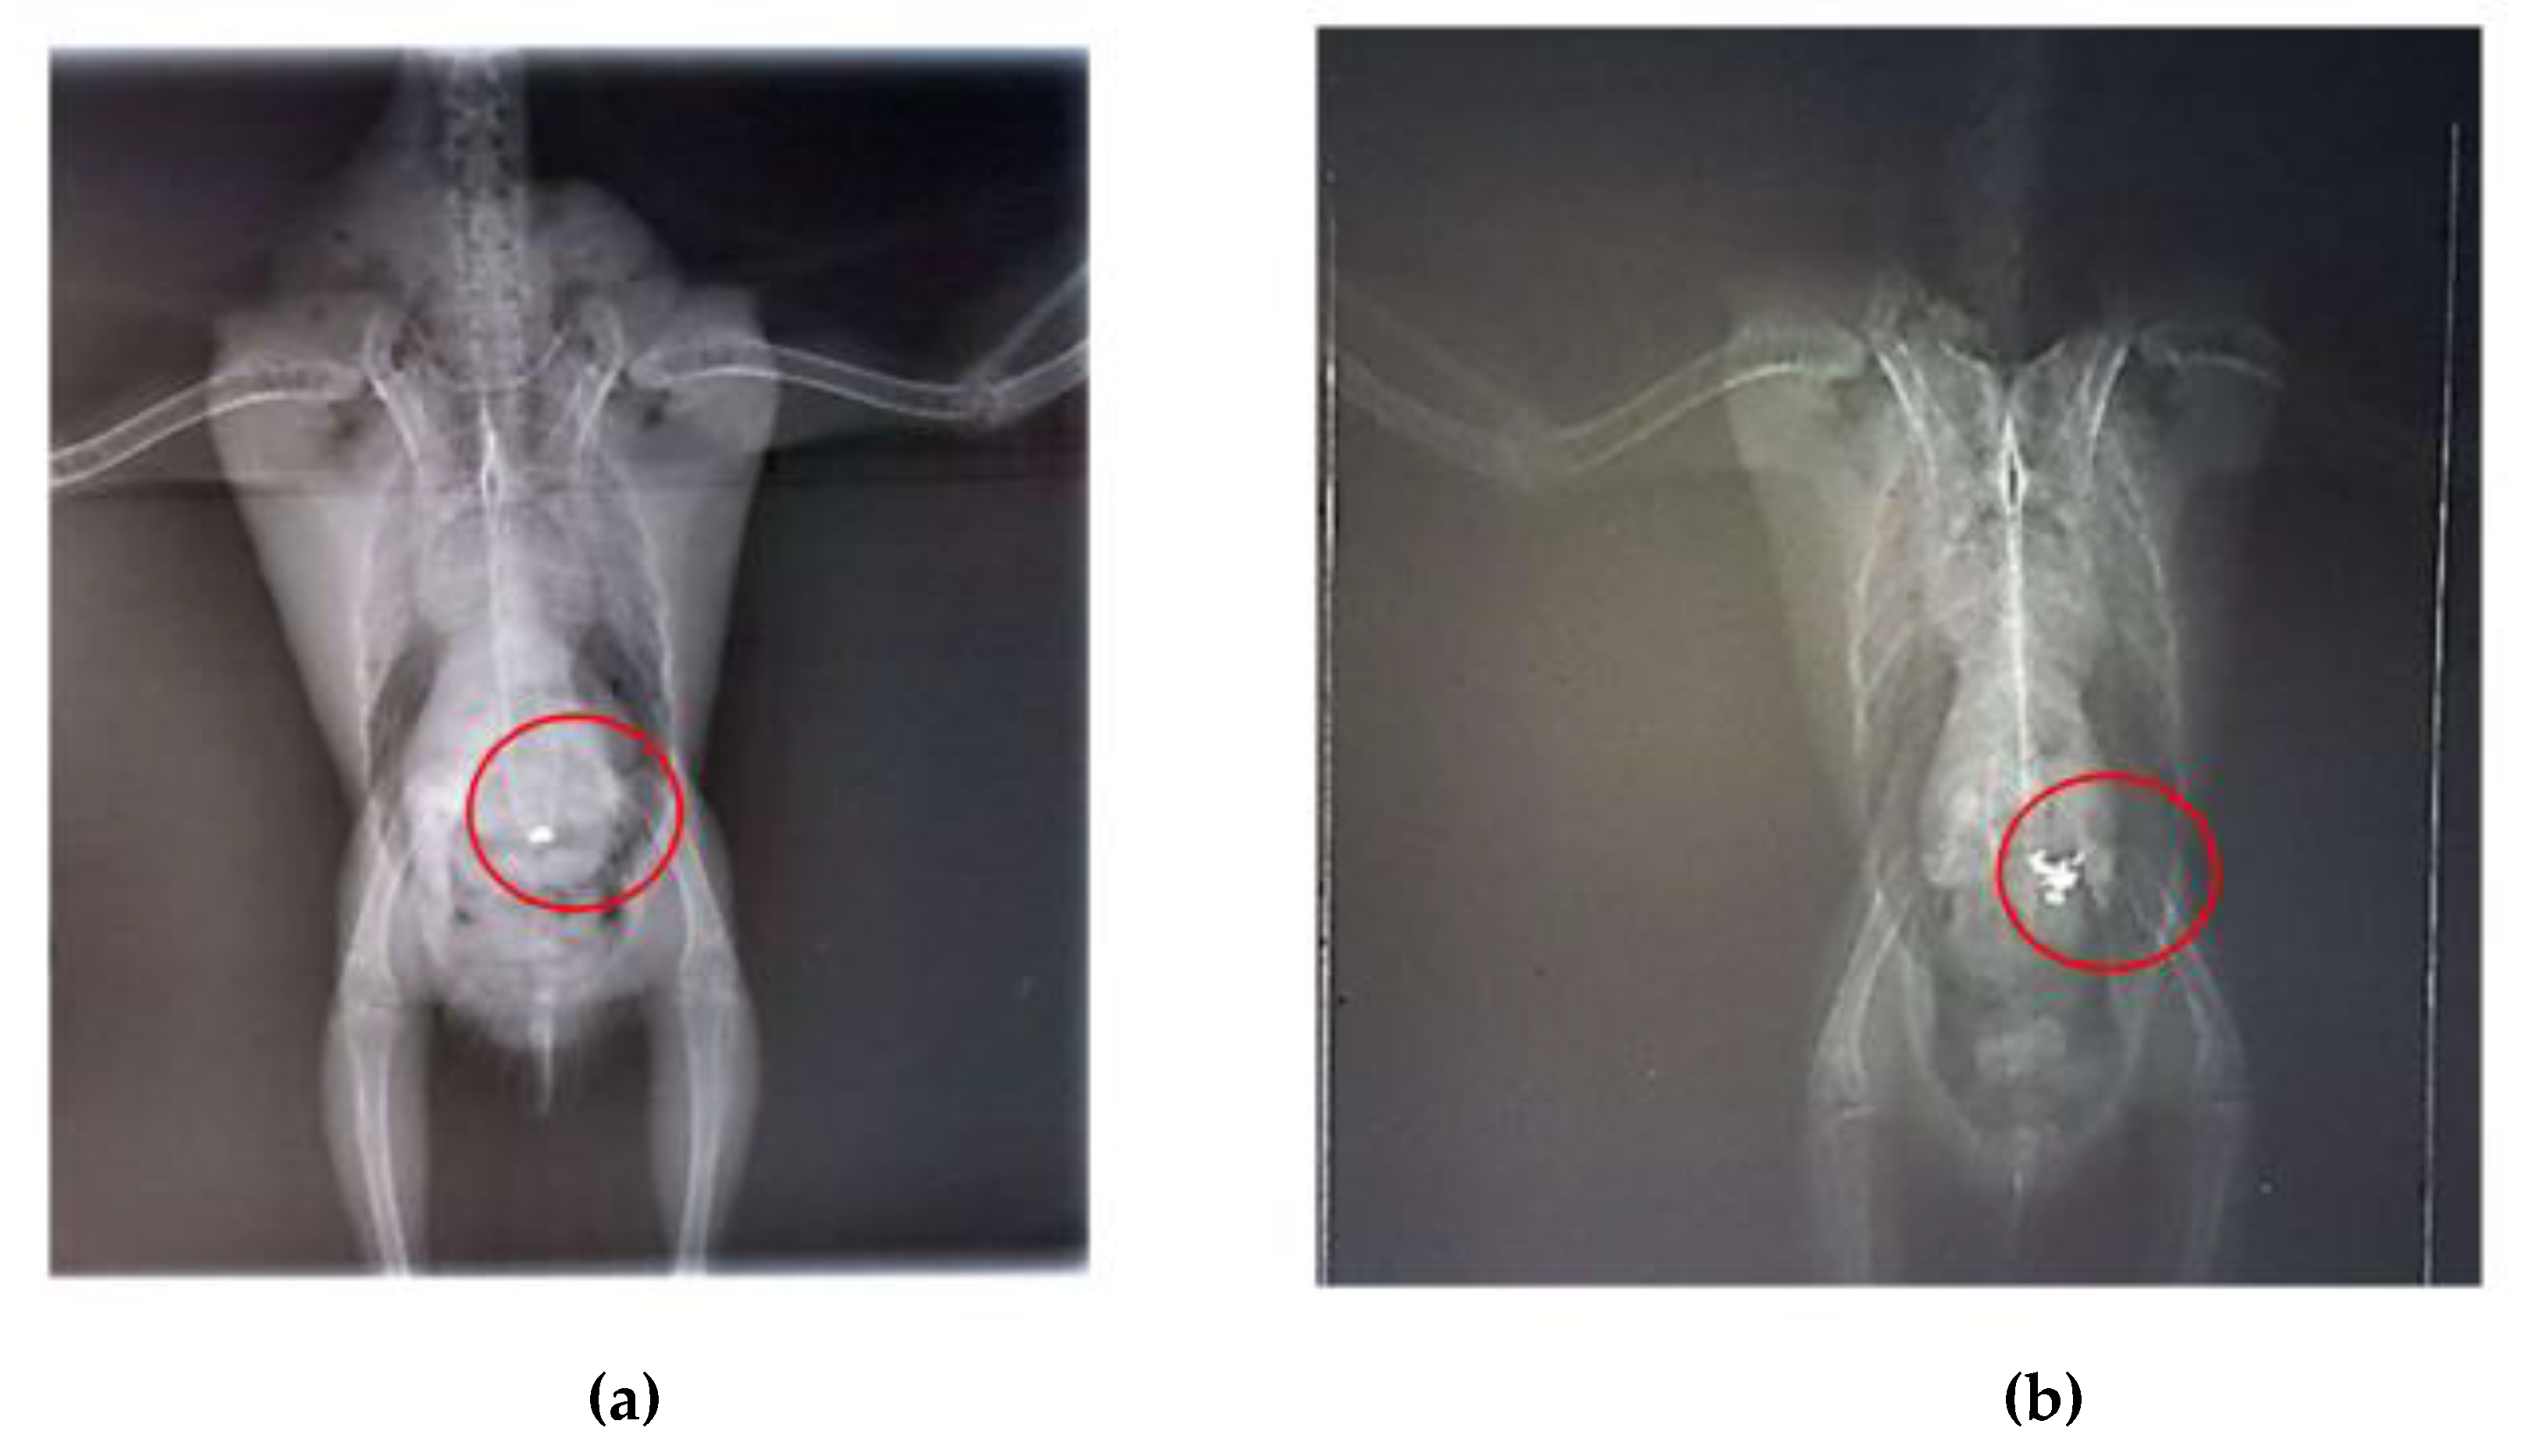

Radiographic examinations revealed a significant accumulation of radiopaque foreign bodies in the ventriculus of both birds, suggestive of metal ingestion (Figure 3A, B and Figure 4A, B). The hematological results are presented in Table 1.

Figure 3. Radiographic examination of the coelomic cavity of Arantiga jandaya (bird 1). (a) Ventrodorsal projection – The heart and liver form a typical hourglass-shaped structure, with pulmonary field radiopacity; dilated ventriculus and proventriculus; radiopaque structures (outlined in red) in the ventriculus region, suggestive of metal content. (b) Right laterolateral projection – Presence of radiopaque foreign bodies (outlined in red), also suggestive of metal.